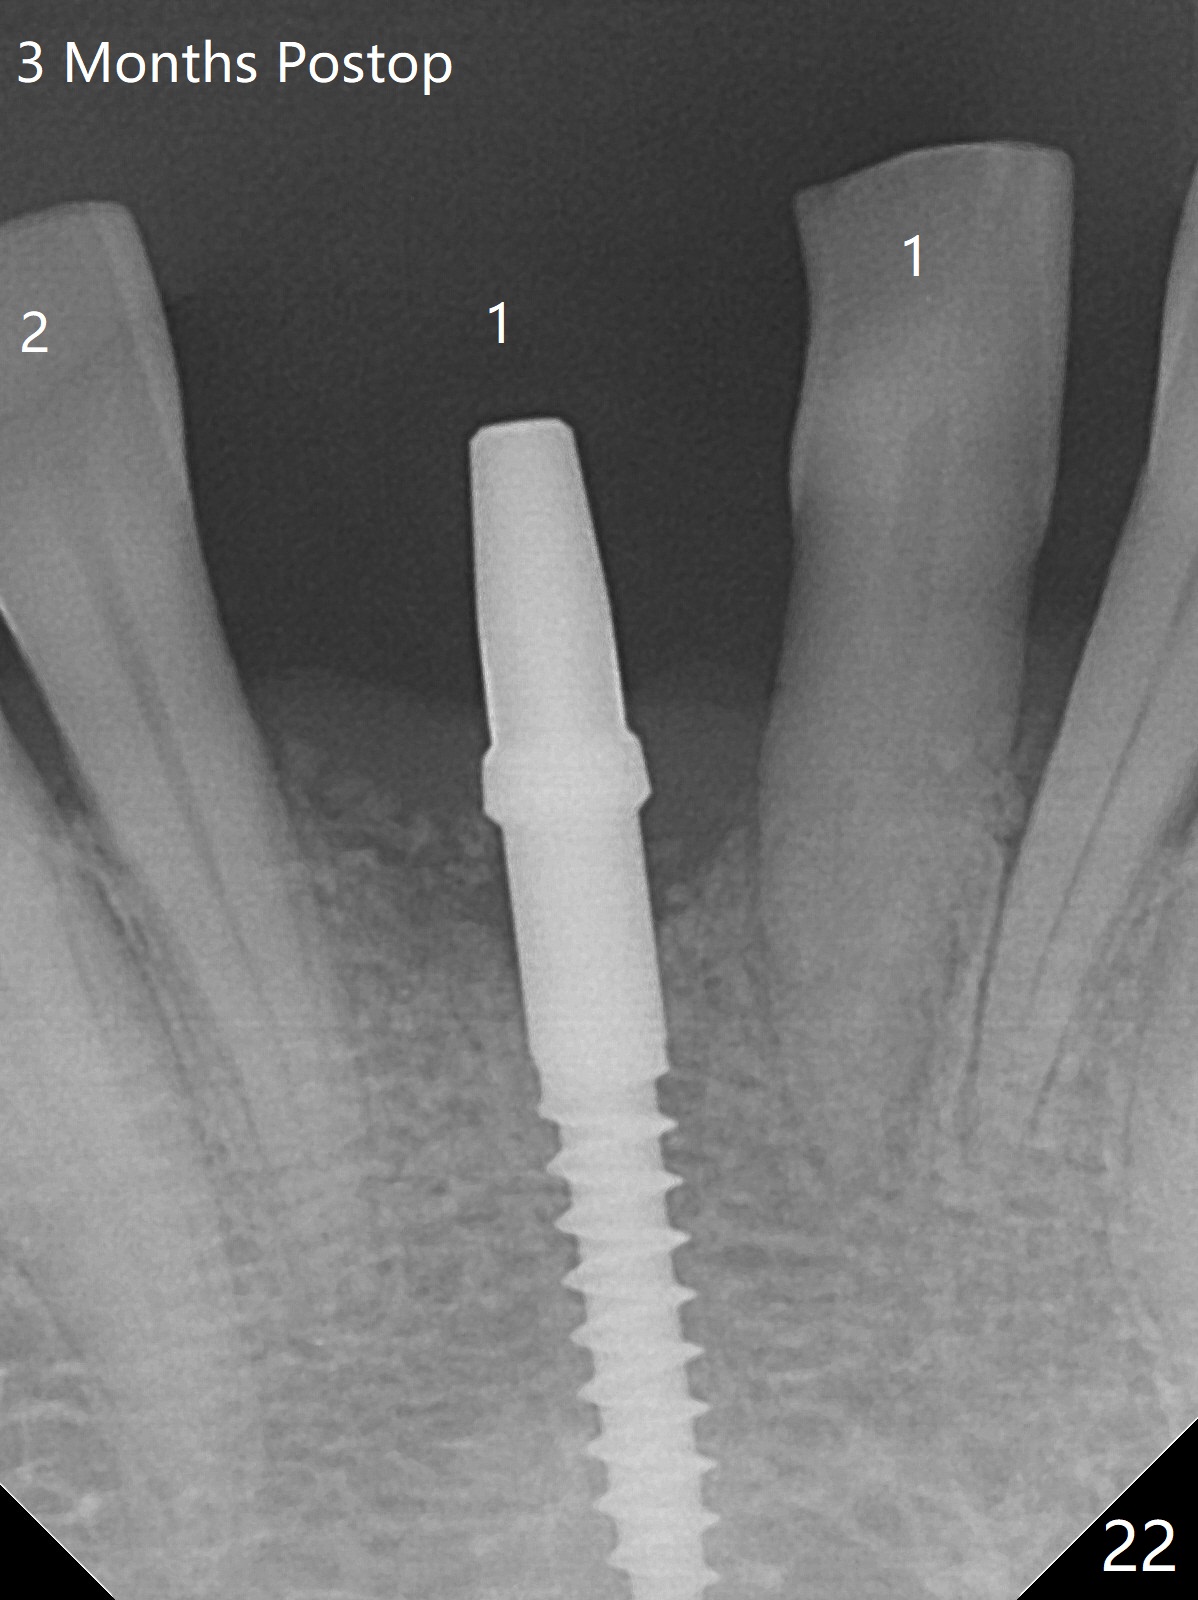

56岁女十分恐惧治疗,缺失右下1,其余切牙由于骨质吸收颊侧移位(图一:1,2),但是她不愿意拔除,同意右下1种植,牙周骨手术,植骨;植体整合后作为支抗,矫正移位下门牙。为了防止忘记舌侧瓣分离,先做舌侧切口(图二),然后颊侧瓣松弛分离(图三),包括使用前牙隧道刀(图四)切断颊侧骨膜,松弛到颊侧瓣能向舌侧牵拉3-4毫米(图五),舌侧瓣骨膜下广泛,深部分离(好像不能切断骨膜,图六),放置导板,磨平狭窄的牙槽嵴(图七:O(osteotomy)),植入2.5x12(4)毫米一段式植体(图八:故意舌侧植入,以便以后矫正),在颊侧骨板打多个出血洞(图八:箭头),然后把在平的器皿上形成的粘性骨板(sticky bone,图九),放置于植体和移位切牙周围(图十),接着使用消毒过的橡皮障punch(图十一(纸头相当于PRF膜;事先给助手示范))在三个PRF膜(图十二)打洞,套在植体和门牙上(图十三: 箭头),防止膜(图十四)和骨块(图十五,十六:*)移位,最后还必须使用最原始方法牙周敷料保护伤口(图十七)。术后9天,舌侧牙周敷料脱落,伤口稍微裂开(图十八)。术后18天撤除敷料,伤口裂开处有新鲜肉芽组织生长(图十九(*:下面是填入的骨粉,将是增宽的牙槽嵴(如果你是乐观主义者)),二十)。病人十分感激我们帮助她度过难关。她的确有sleep apnea,否定tongue thrust。术后三个月植体周围没有明显骨质吸收(图二十一至二十三),左下1,2轻度反合(图二十四),植体周围软组织健康(图二十五),5-5安置矫正器(图二十六,二十七,12 niti)。一周后下切牙向舌侧移动(图二十八),左下1,2反合纠正(图二十九)。再一周变化不大(图三十),植牙圈有些松动,两周后将重做临时牙冠,槽往舌侧移动。结果病人提前回来,植牙槽舌侧移位。一周后右下2不适(图三十一),尝试近中牵引(图三十二)。